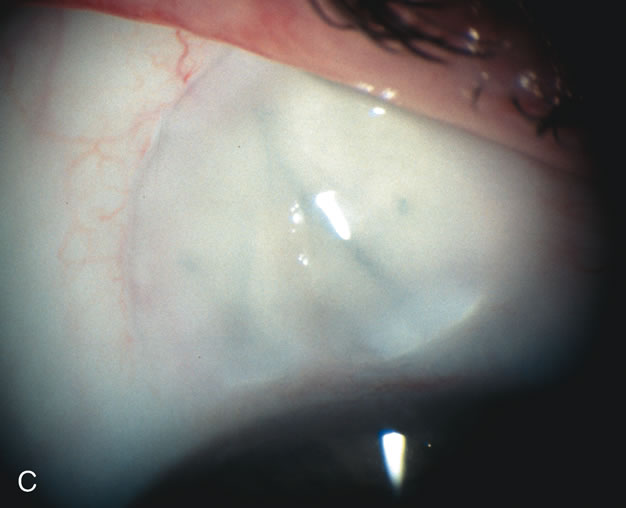

Fig. 8. Bleb appearance after limbus-based versus fornix-based conjunctival flaps. Even though the IOP is thought to be equivalent between limbus and fornix-based conjunctival flaps, the final bleb appearance varies considerably. A. During a limbus-based approach, an incision through conjunctiva 10 mm posterior to limbus will sever through multiple arterial vessels, increasing the likelihood of an avascular bleb. B. The tissues are dissected down to the sclera further cutting feeder vessels from Tenon's capsule. C. The wound is closed inciting a cascade of wound healing events that may ultimately lead to scarring producing a barrier to aqueous flow. D. This leads to walling off of a bleb that has lost some of its overlying vascularity (pale cystic avascular bleb). E. During a fornix-based conjunctival approach, the incision is made at the limbus and tissues undermined. F. The incision is closed at the limbus; no conjunctival vessels are severed over the bleb area. G. This fosters the formation of a shallow diffuse pale bleb with a normal vessel pattern.